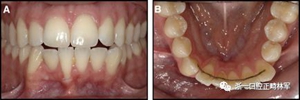

圖17.治療進展:A和B,二次手術后愈合; C和D,幾個月后牙根扭矩的改善。

圖18.脫粘后的最終圖像:A,正面視圖; B,咬合面視圖。 進一步的牙齒移動以糾正輕度前牙開合被認為不符合患者的最佳利益。